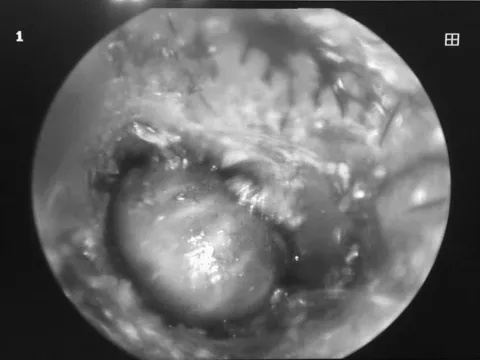

Bác sĩ gắp được ve chó còn sống trong tai bé gái 2 tuổi

Gia đình bệnh nhi 2 tuổi cho hay trước khi vào viện, trẻ có dấu hiệu đau, nhức và chảy dịch ở tai.